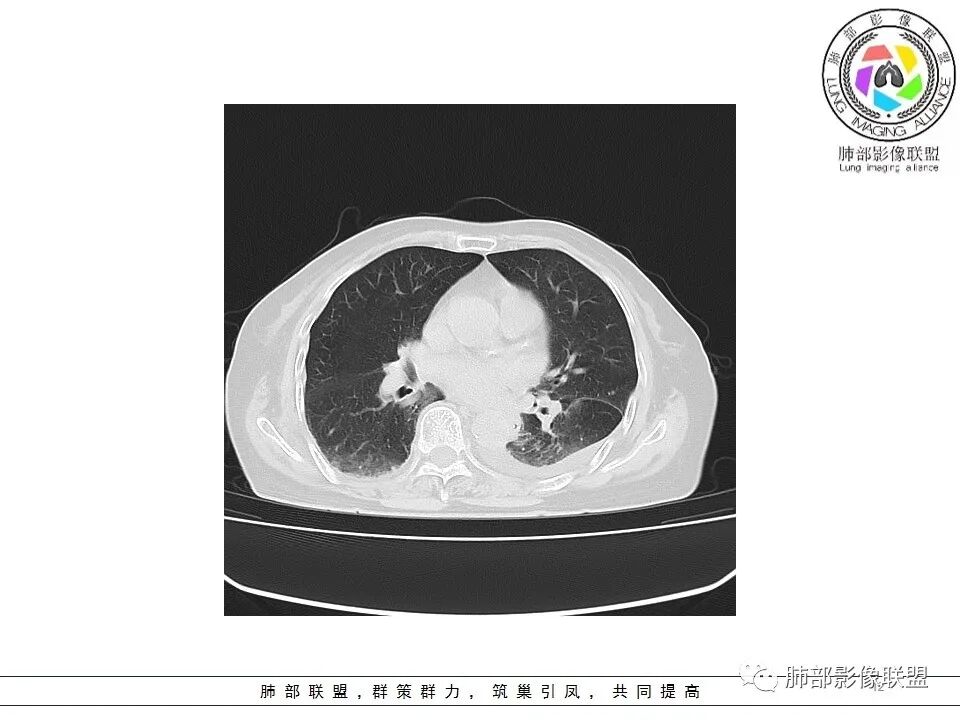

一切∮随缘: 左肺下叶脊柱旁可见大片状实变,跨多个叶段,宽基底与胸膜相贴,胸膜下可见积液,周围伴有空洞,平扫密实欠均匀,增强扫描可见低密度坏死,及血管束穿行,临床:女性,反复咳嗽咳痰7天,余未提示异常,无实验室指标,考虑:慢性脓肿(OP),放线菌?奴卡?腺癌?完善支气管镜,穿刺送培养,病理学检查。

?? 玫: 女,78岁,反复咳嗽,咳痰一周,左侧胸腔积液,贫血,左肺下叶片状实变影,边界清晰,病灶呈宽基底与胸膜相连,病灶内密度不均,增强扫描呈不均匀性强化,病灶内坏死,考虑肺脓肿可能,鉴别鳞癌,腺癌。

不吝慷慨: 左下肺肿块样病变,好像有体循环供血,肿块内血管漂浮,基本走行自然,所以综合考虑肺段隔离症,有低密度坏死区及胸腔积液,考虑合并感染。鉴别一下淋巴瘤

宇宙: 左肺下叶后基底段肿块,边缘毛糙,后基底段支气管阻塞,明显不均匀渐进强化,其内血管清晰自然,可见坏死灶,部分边界清,左侧胸水,考虑炎性病变,鉴别腺癌

飞鹰行动: 女,78岁,反复咳嗽,咳痰七天,左肺下叶纵膈旁团片状实变影,边界清晰,局部膨胀性生长,病灶内密度不均,增强扫描病灶内呈不均匀性强化,部分坏死区边界不清晰,内可见血管造影征,部分坏死区边界清晰,可见环形强化,感染性病变是有的,需要警惕合并占位,腺癌伴感染?

小兜: 女,78岁 反复咳嗽咳痰7天,左肺下叶脊柱旁实变影,平扫密度不均,内部可见低密度灶,增强扫描明显不均匀强化,内部血管走行自然,可见多发低密度坏死区,坏死区边界清晰,少量胸水,考虑脓肿

丽: 老年女性,病程短,左肺下叶实变密度影,边缘模糊不清,增强后明显不均匀强化,内可见坏死,血管走形自然,考虑炎性病变伴脓肿形成

风儿: 老年女性,咳嗽咳痰7。左肺下叶后基底段肿块,边缘毛糙,外缘轻度膨隆,支气管有阻塞,强化不均匀,其内血管清晰自然,可见边缘清晰坏死灶,少量胸水,考虑:炎性-炎症机化伴慢性脓肿、放线菌;肿瘤:腺癌

尘缘: 老年女性,咳嗽咳痰7天,影像表现:左下肺肿块,内部多处坏死,胸腔积液,增强内部血管走行尚可,血管破坏不明显,大的坏死边缘清楚,大的坏死后面一部分不均匀强化,内部边界不规则的坏死,在肿块后方是强化的不张肺组织。思路:初步诊断:1,感染明确,依据,咳嗽咳痰七天,双肺渗出改变,胸腔积液,左下肺脓肿形成,查一下血象,CRP,PCT等炎性指标。2、左下肺肺癌可能较大,依据:大的坏死后面一部分强化不均匀,坏死边界不清,内部血管明显比其他部分减少。外围不张(常规来说腺癌可能更大,但是这个病人肿块外围有强化的不张肺组织,所以鳞癌高度怀疑),3、肺隔离症,这个部位要怀疑,但是提供的影像没有体动脉供血依据,需要结合血管重建明确。4、淋巴瘤,这种肿块伴坏死,胸腔积液的老年女性,要考虑弥漫大B的可能,需要穿刺病理明确。5、整个一元特殊感染,放线菌、结核等等,需要结合口腔清洁情况和NGS明确。综上所述:考虑肺癌(鳞癌>腺癌>其他类型癌)合并感染可能大,鉴别诊断:放线菌感染>淋巴瘤(弥漫大B)>肺隔离症>结核,下一步穿刺活检及NGS。

老年女性,急性发病,短病程病史。左肺下叶实变影,肺叶体积缩小,周围有带状不一致密度影。单独发生于左侧的胸腔积液渗出液多见。   影像上病灶重建后长轴呈楔形,而非类圆形,边缘平直,符合肺叶形态(与横断位膨隆并不一致),从整体形态上支持炎性病变;   病灶内血管走形自然,无受侵犯、受推移迹象,不大符合鳞癌等破坏性较强的肿瘤性病变。女性患者鳞癌也少见。   病灶内坏死腔内壁清楚光滑,薄环状强化带,支持炎性、尤其是化脓性病变。肺腺癌这样的坏死少见。   病灶近端支气管虽然堵塞,但是支气管走形自然,壁无明显破坏,腔内粘液栓堵塞为主,病灶外周大,内带小,局部无膨隆迹象,不符合近端支气管肺癌堵塞所致表现;也不符合外周肿块朝内带推进表现。   综合分析:符合炎性病变,不支持恶性肿瘤性改变